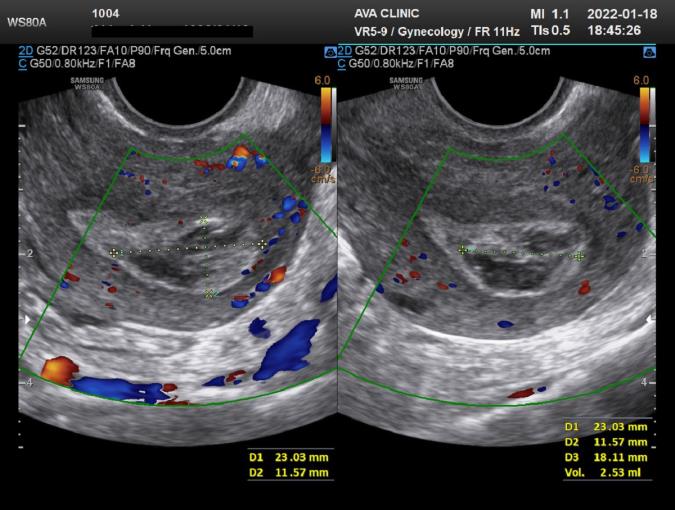

سونوگرافی بقایای بارداری چگونه انجام می شود؟

دو نوع اصلی سونوگرافی از جنین و بقایای آن وجود دارد که شامل موارد زیر می باشد:

سونوگرافی ترانس واژینال

در این نوع سونوگرافی مبدل درون واژن قرار می گیرد تا امواج صوتی را ارسال نموده و بازتاب ها را جمع آوری کند. سونوگرافی های واژن اغلب در اوایل بارداری استفاده می شوند. همچنین درصورتی که سونوگرافی شکمی اطلاعات کافی را ارائه ندهد ممکن است از این نوع سونوگرافی نیز استفاده شود.

سونوگرافی ترانس شکمی

این نوع تصویربرداری با حرکت دادن مبدل بر روی شکم انجام می شود. سونوگرافیست کمی ژل التراسونیک را روی پوست شکم ریخته و مبدل کوچک سونوگرافی که دارای فرکانس کمتر اما عمق نفوذ بیشتری است را بر روی شکم حرکت می دهد تا تصاویر بر روی مانیتور رایانه ظاهر شود.